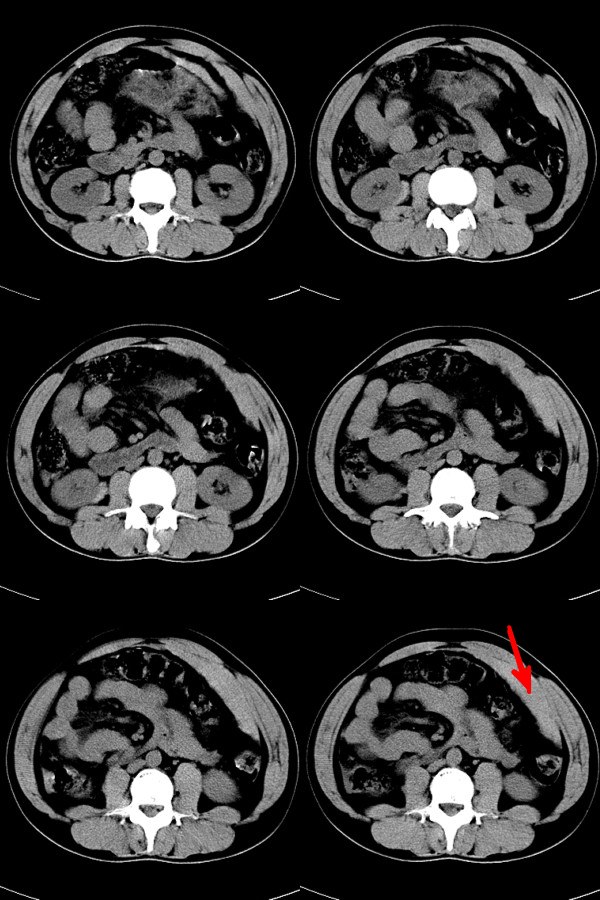

请指教红色箭头所示为什么影像?

红箭所示为腹膜腔积血

腹膜腔积血,考虑:腹腔脏器损伤!

红箭示血肿,脾破裂,右肾包膜下血肿.

箭头为腹膜外血肿;;建议使用w300---500;l负50--70,可清晰显示腹腔游离气液影,有利空腔器官破裂诊断

右肾包膜下也有血肿吧